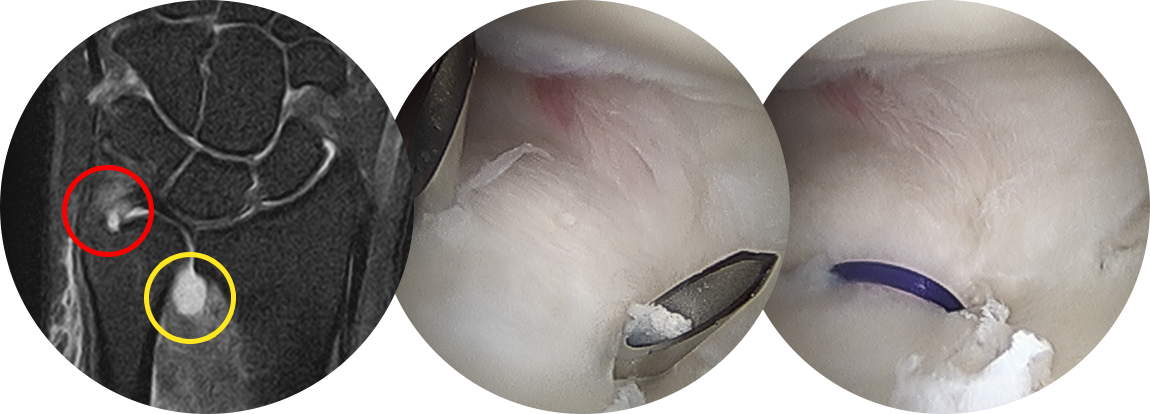

관절경 시야에서 삼각섬유연골복합체의 파열을 직/간접적인

방법을 통해 확진을 하게 됩니다.

파열된 인대를 뼈에 부착시켜주기 위하여 골터널을 이용하여

실을 통과시켜 뼈에 단단하게 삼각섬유연골복합체 봉합을 시행합니다.

삼각섬유연골복합체 파열이 있을 경우 MRI 에서 다음과 같이 뼈 부착부에서의 파열(빨간 원)과

관절액이 원위요척관절로 새어 나온 이차적인 변화(노란 원)이 관찰됩니다.

뼈에서 부터 바늘이 나오도록 하여 바늘을 통해 실을 통과 시킨 후 단단하게 봉합해줍니다.

봉합 전, 후 석션 검사를 비교하여 삼각섬유연골복합체가 안정화 된 것을 확인할 수 있습니다.